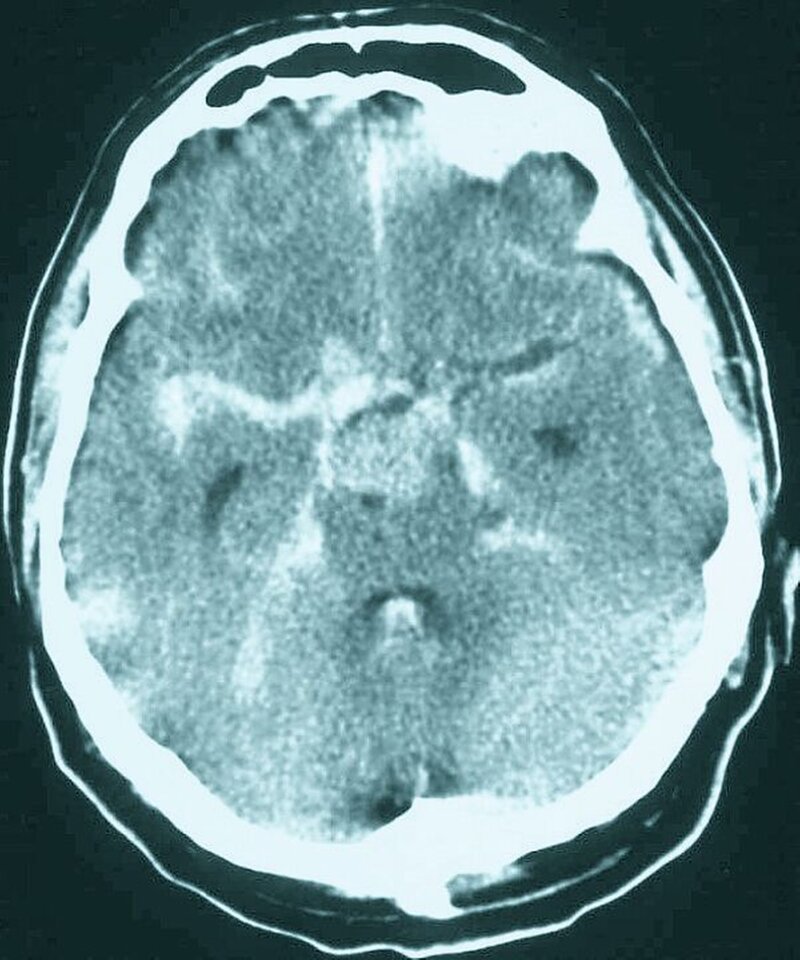

In der akuten Phase entspricht die Therapie einer TIA der des Schlaganfalls, da zu diesem Zeitpunkt eine Unterscheidung nicht möglich ist. Ob hinter einer Schlaganfallsymptomatik wiederum eine Minderdurchblutung oder eine Blutung steht, ist anhand der klinischen Symptomatik ebenfalls nicht zu sehen. Die Unterscheidung zwischen Minderdurchblutung und Blutung ist allerdings wegweisend für den weiteren Therapieverlauf. Erst eine geeignete Bildgebung (CT) ermöglicht den Ausschluss einer Blutung und erlaubt die Indikationsstellung für eine Lysetherapie. Dieser Umstand schränkt somit die Therapiemöglichkeiten im Sinne einer Erstversorgung im Vorfeld der Klinikeinweisung stark ein. Zunächst sollten andere Ursachen neurologischer Ausfallerscheinungen ausgeschlossen werden. Hierzu gehören eine mögliche Hypoglykämie und Krampfanfälle anderer Genese, etwa im Rahmen einer bestehenden Epilepsie. Des Weiteren sollte eine hypertensive Krise in die differenzialdiagnostischen Überlegungen mit einbezogen werden. Gelegentlich treten TIAs auch bei anderen Erkrankungen wie der Migräne auf, dies spielt allerdings für die Notfalltherapie keine Rolle.